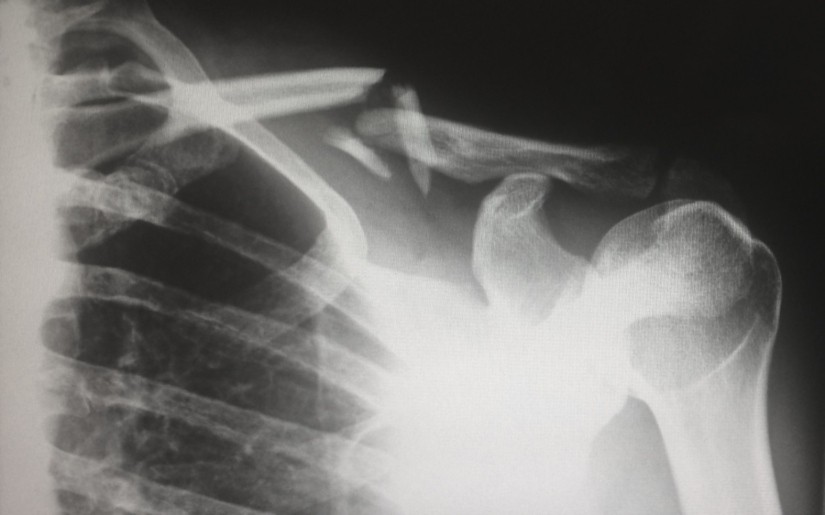

The mineral content of our bones is measured as Bone Mineral Density (BMD). Lower levels leave the bone more vulnerable to fractures and bone conditions such as osteopenia, which can then develop to osteoporosis.

What Is Osteoporosis?

Osteoporosis is a weakening of the bones so that they become brittle. It is most often found in people who are over 20 years of age who are not getting enough of the right vitamins to ensure the strength of their bones. It is also more common in older people and women, particularly those who have early menopause or who have had a hysterectomy.